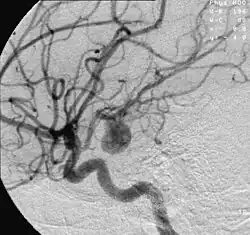

Tętniak (łac. aneurysma, ang. aneurysm lub aneurism z gr. ana- w górę, więcej, eurys szeroki, aneurynein rozszerzać) – wypełnione krwią, ograniczone poszerzenie światła naczynia krwionośnego (tętnicy, wyjątkowo rzadko żyły). Mają kształt wrzeciona lub worka, są lokalnie ograniczone, cechuje je powiększenie poprzecznego przekroju tętnic (rzadko żył) w wyniku wrodzonych lub nabytych zmian ściany. To odróżnia tętniaka od ektazji, na przykład trwałe poszerzenie naczyń krwionośnych (i narządów pustych), które rozwinęło się pomimo nienaruszonego stanu wszystkich zaangażowanych warstw ścian. Tętniak, zwłaszcza gdy pęknie, stanowi poważne zagrożenie dla zdrowia i życia[1].

- tętniak tętnic mózgowych